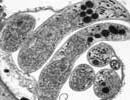

Cryptosporidium hominis UdeA01

Courtesy of Saul Tzipori, Tufts

| Comment: | Cryptosporidium hominis is the dominant species which infects humans. Although generally self-limiting, this disease can cause fatalities in children and immunocompromised adults. The genome sequence of Cryptosporidium hominis shows features consistent with its life cycle as an obligate parasite. This organism lacks the genes necessary for the production of a number of biochemical building block such as nucleotides and amino acids. To compensate for this lack, the genome contains a large number of transporter or transporter-like genes. |